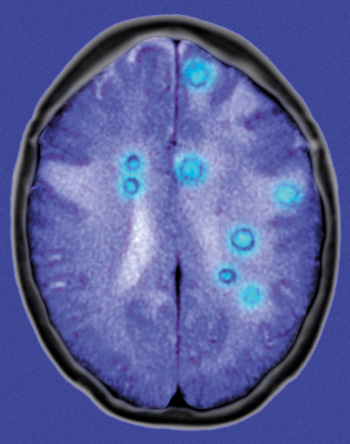

Medulloblastomer er studert i to musemodeller og i et klinisk materiale ved hjelp av avanserte molekylærbiologiske metoder (1). Mutasjoner i primærtumoren gjorde den heterogen, og det var en liten subklon av cellene som metastaserte via cerebrospinalvæsken til leptomeningene. Ytterligere mutasjoner kom til. De var forskjellige i primærtumoren og i metastasene, men metastasemutasjonene var for en stor del de samme i den enkelte mus/pasient. Dette kan bety at et medikamentelt terapeutisk angrepspunkt i primærtumoren ikke gjenfinnes i metastasene – og det er som oftest de som tar livet av pasienten.

– Funnene fra medulloblastomer er svært interessante, men ikke unike, sier professor Gunhild M. Mælandsmo, Institutt for kreftforskning, Oslo universitetssykehus. – Også i brystkreft vet vi at molekylære endringer i primærtumoren ikke nødvendigvis gjenspeiles i metastasene. Den rådende hypotesen er at primærtumoren er svært heterogen og at noen kloner har større evne til å invadere og dermed gi opphav til metastaser. De molekylære forskjellene mellom primærtumor og metastaser forsterkes videre ved at celler i begge lokalisasjoner akkumulerer nye mutasjoner.

Moderne kreftbehandling vil i økende grad bli tilpasset den enkelte pasient. Denne utviklingen drives av teknologiske fremskritt – for eksempel sekvenseringsteknologi, som angir hvilke mutasjoner som finnes i en tumor, og av nye medikamenter rettet inn mot slike molekylære angrepspunkter. Disse nye funnene understreker behovet for å karakterisere de molekylære endringene i metastasene og ikke basere valget av terapi for metastatisk sykdom kun på funn gjort i primærtumoren. Slik vil målrettet kreftbehandling ha potensial til å bli langt mer effektiv enn den er i dag, sier Mælandsmo.